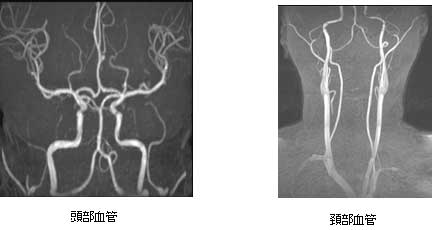

頭部領域

頭部領域では、様々な撮影法を組み合わせて診断する事で、脳梗塞、脳腫瘍、脳出血、その他の変性疾患の評価に有用です。

また、造影剤を使用する事なく血管を描出する事ができ、脳動脈瘤、血管の狭窄や塞栓の診断に力を発揮します。